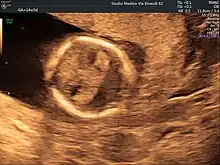

Holoprosencephaly is typically diagnosed during fetal development when there are abnormalities found on fetal brain imaging, however it can also be diagnosed after birth. The protocol for diagnosis includes neuroimaging (Ultrasound or fetal MRI prior to birth or Ultrasound, MRI or CT post birth), syndrome evaluation, cytogenetics, molecular testing, and genetic counseling.[3]